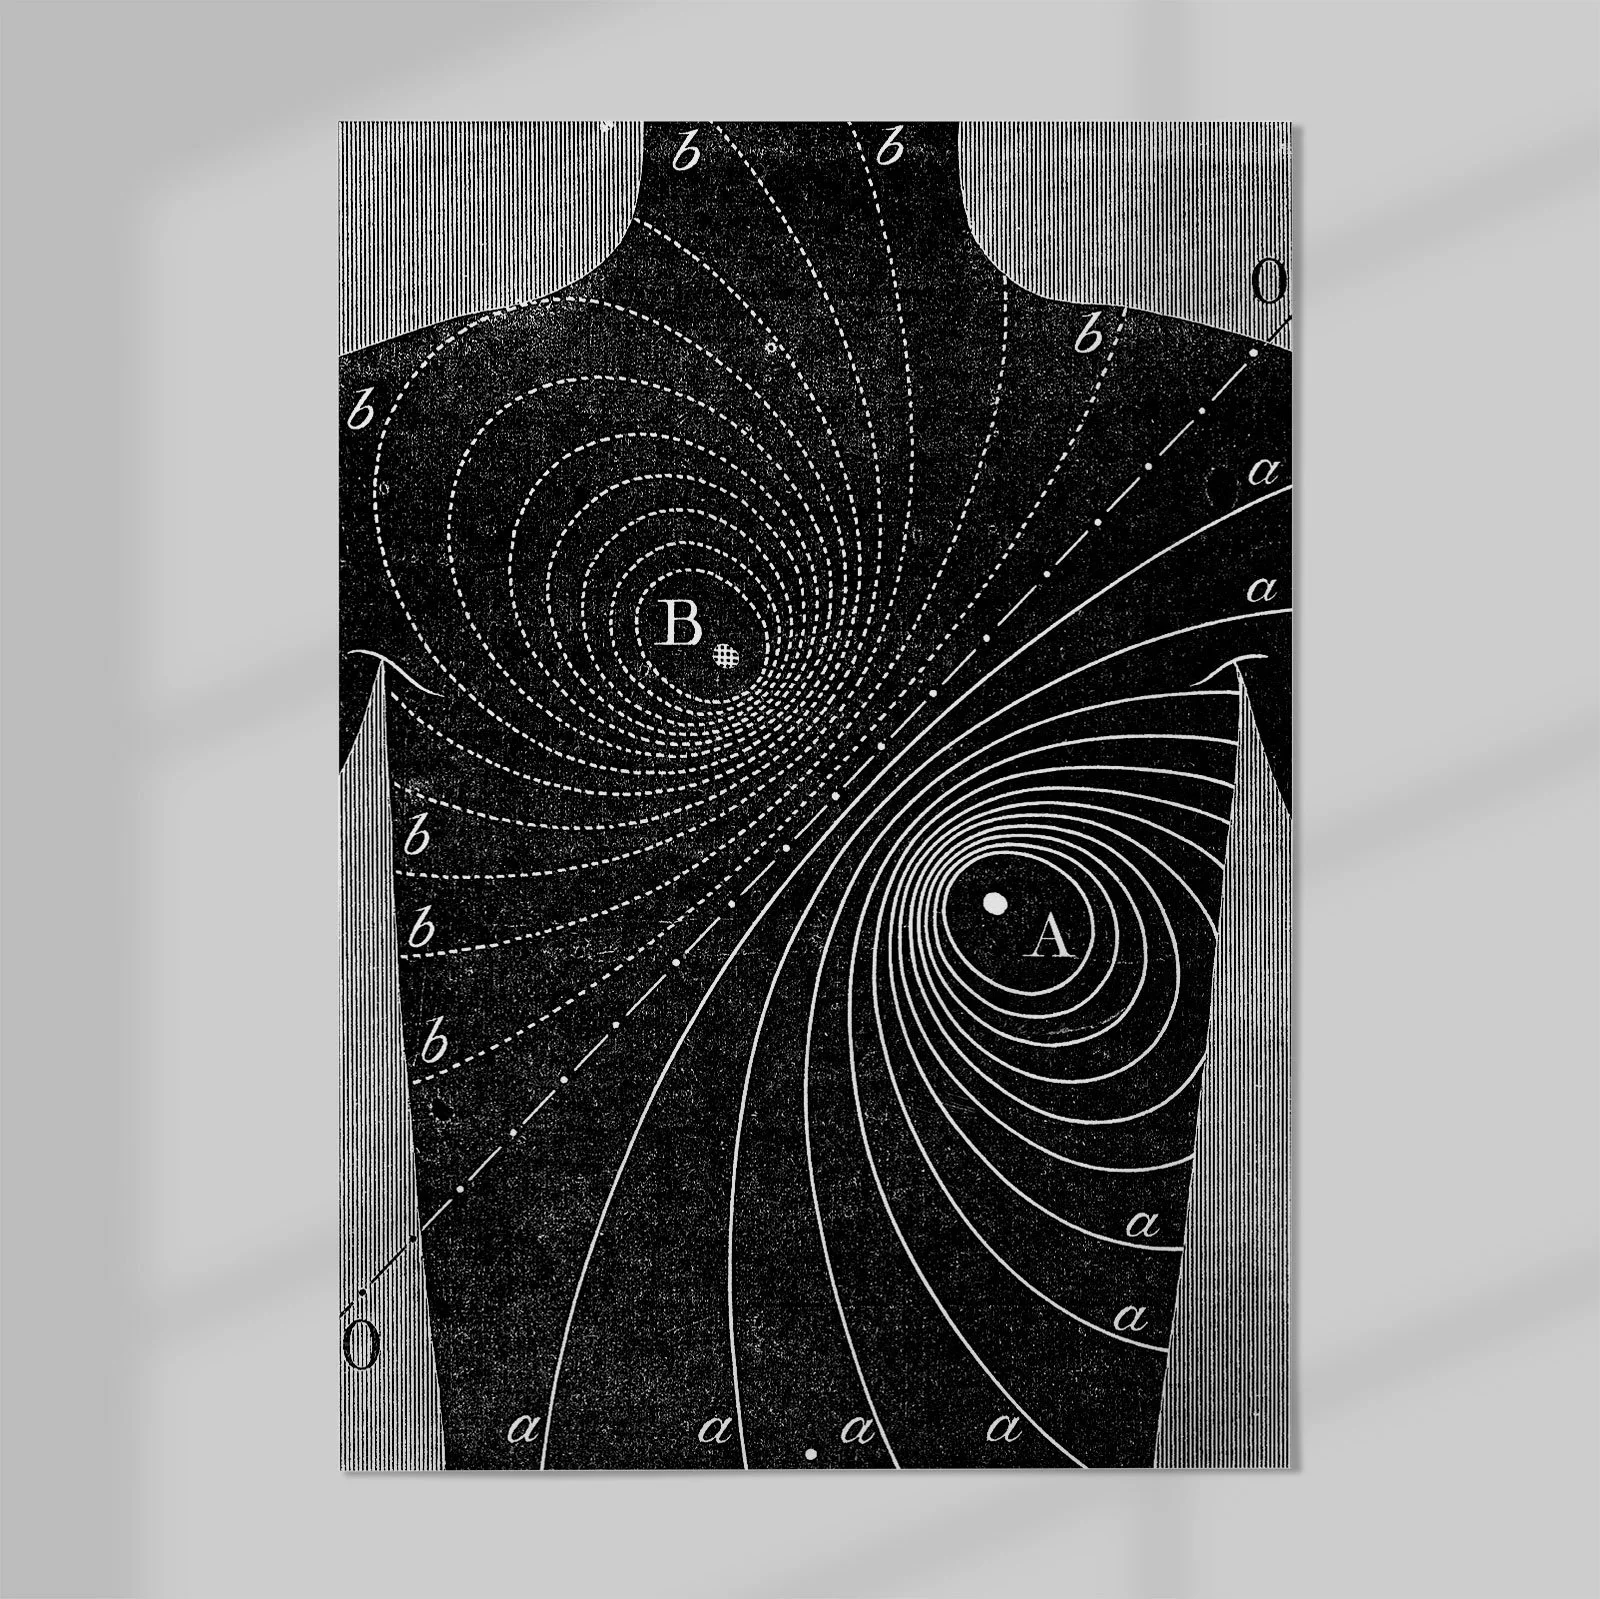

Properties of Human Heart by Augustus Waller 1888

Plate from Augustus D. Waller’s Introductory Address on the Electromotive Properties of the Human Heart.

Augustus Desiré Waller (18 July 1856 – 11 March 1922) was a British physiologist renowned for his pioneering work in electrocardiography. In 1887, he recorded the first human electrocardiogram using a capillary electrometer. He went on to develop the first practical ECG machine with surface electrodes and presented his work across Europe and America—often using his dog, Jimmy, in live demonstrations.The Bull by Franz Marc (1912)